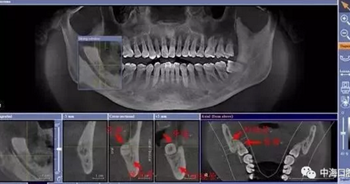

由于智齒的生長位置特殊,導致了拔除難易不同,如智齒出現(xiàn)橫著長或者靠近牙神經的話,則難度會較高,一般人只需拍個口腔全景片,但相對于智齒靠近神經管的情況,還可能需要拍CT,這都很考驗牙醫(yī)的技術。

拔牙非小事,請不要拿成本衡量牙醫(yī)的價值!

下面這兩張圖,據(jù)說拔牙費時1.5小時,收費14000元。